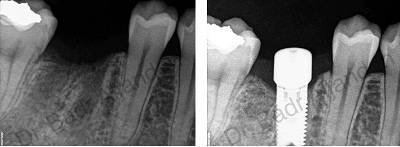

The implants themselves are tiny titanium posts, which are inserted into the jawbone where teeth are missing. These metal anchors act as tooth root substitutes. They are surgically placed into the jawbone. The bone bonds with the titanium, creating a strong foundation for artificial teeth. Small posts are then attached to the implant, which protrude through the gums. These posts provide stable anchors for artificial replacement teeth.

For most patients, the placement of dental implants involves two surgical procedures. First, implants are placed within your jawbone. For the first three to six months following surgery, the implants are beneath the surface of the gums gradually bonding with the jawbone. You should be able to wear temporary dentures and eat a soft diet during this time. At the same time, your dentist is forming new replacement teeth.

After the implant has bonded to the jawbone, the second phase begins. Dr. Al-jandan will uncover the implants and attach small posts that protrude through the gums and will act as anchors for the artificial teeth. When the artificial teeth are placed, these posts will not be seen. The entire procedure usually takes six to eight months. Most patients experience minimal disruption in their daily life.

Using the most recent advances in dental implant technology, Dr.Al-jandan is able to place single stage implants. These implants do not require a second procedure to uncover them, but do require a minimum of six weeks of healing time before artificial teeth are placed. There are even situations where the implants can be placed at the same time as a tooth extraction – further minimizing the number of surgical procedures.